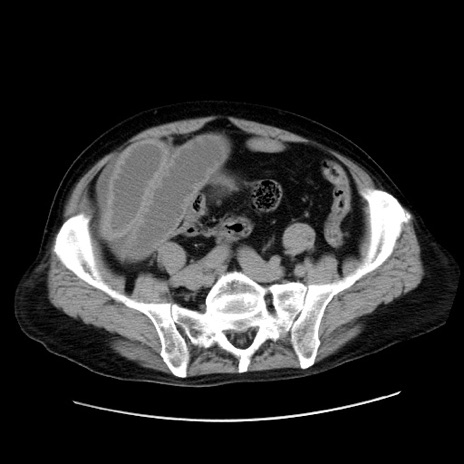

症例30(横断像)

【症例】80歳代男性

【主訴】臍周囲痛

【現病歴】約6時間前から臍下部痛が出現。次第に腹部膨隆・背部痛も生じてきたため来院。背部痛の場所は変化しない。

【身体所見】意識清明、BT 36.3℃、BP  131/87mmHg、P 87bpm、SpO2 100%(RA)、臍周囲自発痛・圧痛あり、反跳痛なし、自発痛部位に一致して板状硬あり、腹部膨隆、腸雑音減弱、CVA tenderness両側陰性。